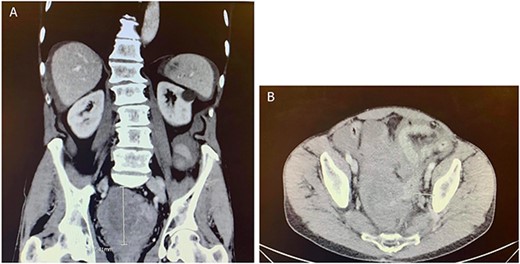

Two months after the tumor was grossly resected and 1 month into Imatinib treatment, the patient presented to the Emergency Department with complaint of abdominal discomfort, constipation and nausea. CT abdomen and pelvis noted mid small bowel distention, suggestive of partial small bowel obstruction with mild ascites. Importantly, a mass-like focus measuring 5 × 3.8 cm was found in the pelvis anterior to the rectosigmoid junction (Fig. 3). A nasogastric tube was subsequently placed and the patient was administered empiric antibiotics. Considered a failure of conservative management, the patient was taken to the operating room again for an exploratory laparotomy, lysis of adhesions and debulking of the mass. The patient tolerated the procedure well with no complications. The patient maintained a typical postoperative course and was discharged with oncological follow-up and continued Imatinib treatment. On 2 and 4 months follow-up CT, the pelvic mass measured 4.1 × 3.3 and 2.6 × 2.7 cm (Fig. 4), respectively.

CT abdomen and pelvis at (A) 2- and (B) 4 months follow-up. The pelvic mass measured 4.1 × 3.3 and 2.6 × 2.7 cm, respectively.